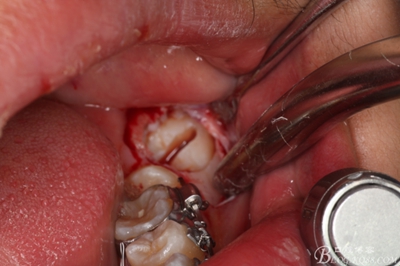

圖9.高速拔牙手機(jī)去骨

9_副本.jpg

圖10.去骨后暴露出38的牙冠